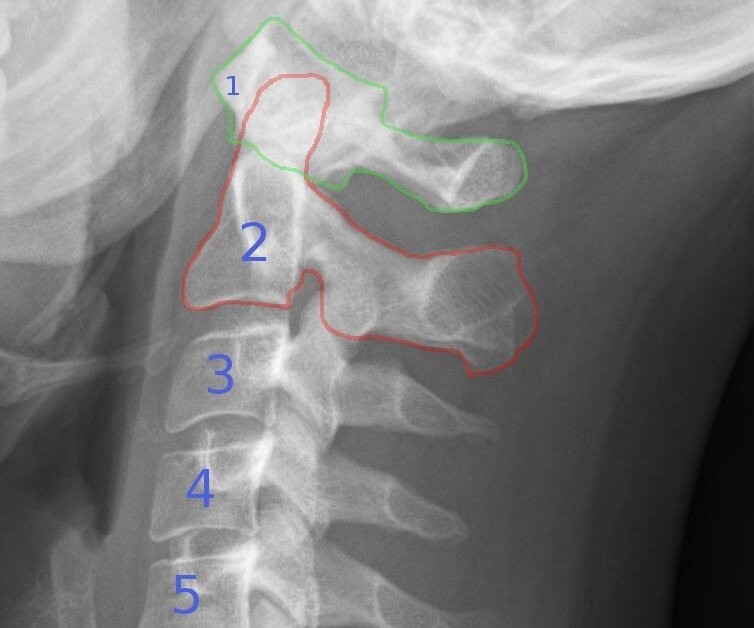

Aufbau der Halswirbelsäule

Die Halswirbelsäule (HWS) besteht aus den obersten 7 Wirbeln der Wirbelsäule. Die obersten beiden, Atlas und Axis, sind im Bild grün bzw rot markiert. Die Halswirbelsäule ist leicht nach vorne gebogen (physiologische Lordose), was normal ist.